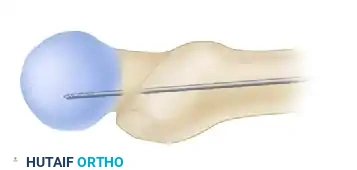

- Localize the entry point with a guide pin on the medial aspect of the greater trochanter.

- Insert the guide pin 2 to 3 cm distally into the proximal fragment.

At this juncture, utilize fluoroscopy to rigorously assess the guide pin placement in both AP and lateral planes.